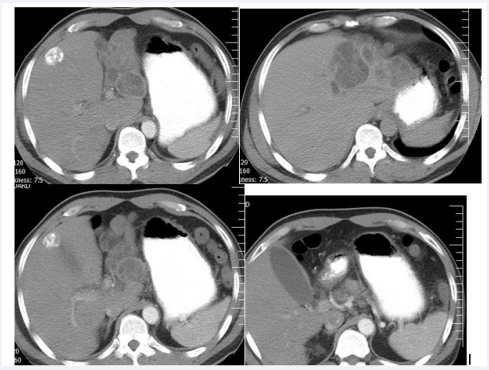

A 52-year-old man with history of previously hydatid cyst of left lobe of liver calcified stage 3 to4 stage presented to hospital with a two-day history of sever colicky abdominal , right upper quadrant pain and vomiting. Four year earlier, he had hydatid cyst of liver which treatment with albendasol and not increased the size of cyst but mild calcified present in the wall of cysts. On examination, he was alert and with scleral icterus. On abdominal examination, right upper quadrant and epigastric tenderness present. Patient complaint of dark urine. Other examination was normal. Laboratory liver tests showed , aspartate transaminase 153 [normal < 40] U/L, alanine transaminase 318 [normal < 41] U/L, alkaline phosphatase 554 [normal 38-126] U/L , amylaseand lipase were in normal range , total bilirubin was 6mg /li,direc bilirubin was 4mg mm /lt ,indirect was mm/lt 2.WBC=13500 with 40% eosinophilia. Abdominal ultrasonography showed a distended and edematous of gallbladder without stone, common bile duct was dilated (diameter was 12 mm). A computed tomography scan of the abdomen without contrast also showed multiple cyst with calcification of cysts wall and all were intact in left lobe of liver, gallbladder was distend without stone (Figures 1-4).

Figure 1-4: Show calcified hydatid cyst of left of liver with distended gall bladder (Albendazol therapy 5 and 3 years ago).